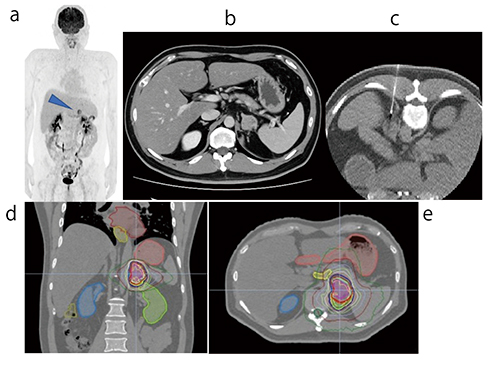

当院では,Radixact Synchrony導入を契機に,腹部腫瘍に対する定位照射を開始した。原発性肝がん,腎がん,前立腺がんだけでなく,オリゴ転移に対する定位放射線治療が保険収載されたことにより,各腹部臓器への定位照射のニーズが高まっている。腹部腫瘍では,腫瘍そのものをkV X線画像で認識できないため,フィデューシャルマーカーが必須である(図5)。特に上腹部病変の場合では,腫瘍は呼吸性に移動することから,動体追尾照射を行うことでPTVとリスク臓器の重複体積を減少することができる。

図5 副腎腫瘍に対する動体追尾照射例

FDG-PET画像では副腎のみのオリゴ転移であった (a▶,b)。フィデューシャルマーカー挿入後に,動体追尾での定位照射を実施した(d,e)。なお,副腎腫瘍でのフィデューシャルマーカーは適応外使用となる(c)。